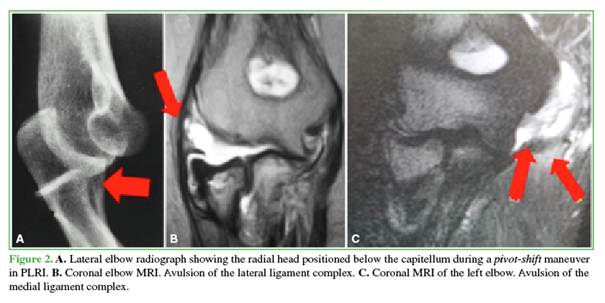

Standard AP and lateral elbow radiographs are generally sufficient initially. CT helps delineate fractures. MRI is seldom obtained in the acute phase; we reserve it for later, once treatment has begun, to characterize soft-tissue injuries (Figure 2).